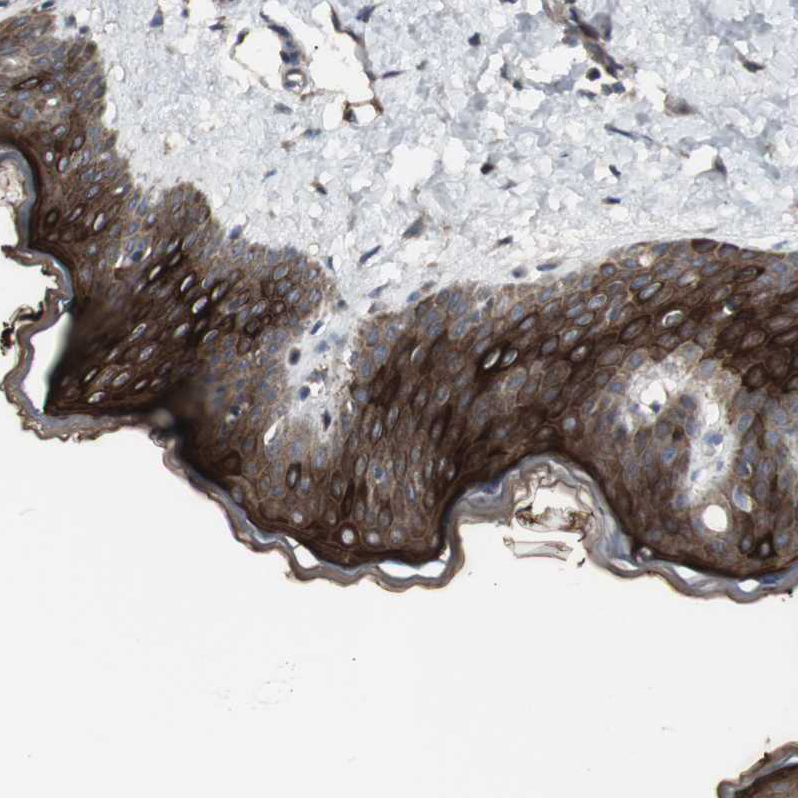

Immunohistochemical staining of human esophagus shows strong cytoplasmic positivity in squamous epithelial cells.